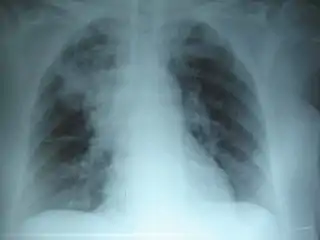

Radiografía de tórax de una neumonía causada por influenza y Haemophilus influenzae, con consolidaciones parcheadas, principalmente en el lóbulo superior derecho (flecha). | ||

La neumonía es, por lo general, la infección aguda del parénquima pulmonar asociada a un nuevo infiltrado en la radiográfica de tórax. La neumonía puede afectar a un lóbulo pulmonar completo (neumonía lobular), a un segmento de lóbulo, a los alvéolos próximos a los bronquios (bronconeumonía) o al tejido intersticial (neumonía intersticial). La neumonía hace que el tejido que forma los pulmones se inflame, se hinche y provoque dolor. Muchos pacientes con neumonía pueden ser tratados de forma ambulatoria sin requerir ingreso hospitalario.

El diagnóstico de neumonía se fundamenta tanto en la clínica del paciente como en resultado de la radiografía de tórax (Rx). Generalmente se usan Rx de tórax (posteroanterior y lateral), analítica sanguínea y cultivos microbiológicos de esputo y sangre.[29] La radiografía de tórax es el diagnóstico estándar en hospitales y clínicas con acceso a rayos X.[30][31]

En personas afectadas de otras enfermedades (como sida o enfisema) que desarrollan neumonía, la Rx de tórax puede ser difícil de interpretar. Un TAC u otros test son a menudo necesarios en estos pacientes para realizar un diagnóstico diferencial de neumonía.